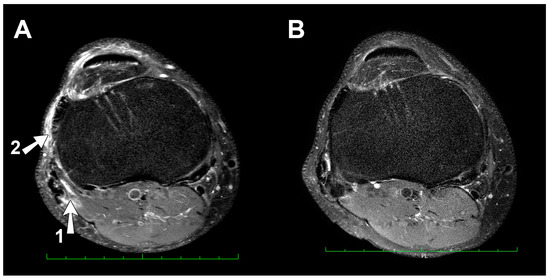

- (a)

- Right knee MRI: One day after 24-h UM run

- (b)

- Right knee MRI: three years later